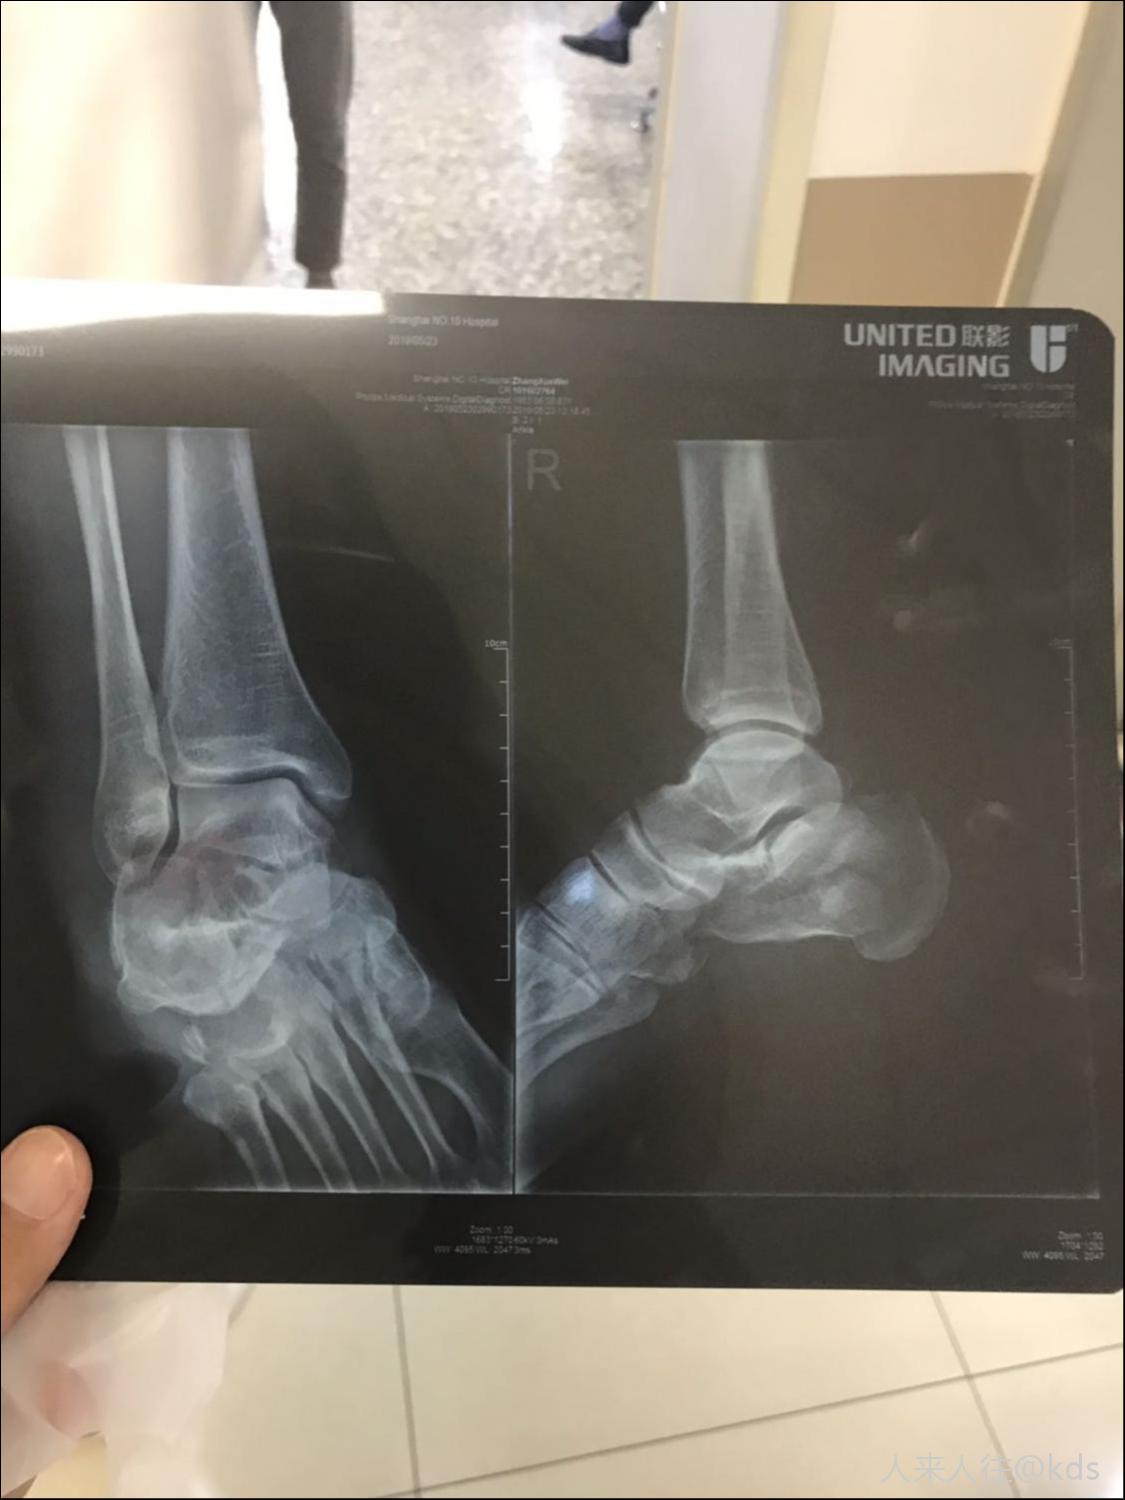

63,刚拿到片子

图片尺寸1125x1500